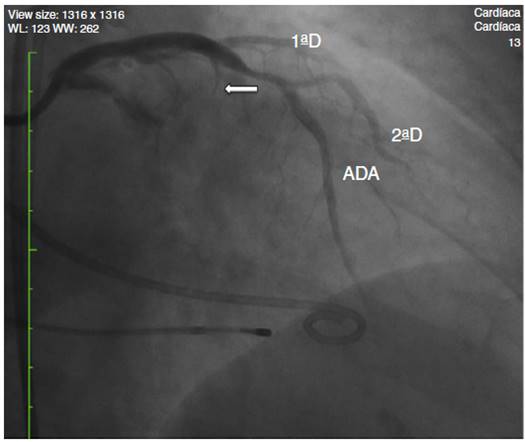

Mientras se mantenía inflado del balón a 6 ATM se pasaron 1,5 ml de alcohol (etanol al 98%) durante 5 minutos, después de los cuales se mantuvo inflado 5 minutos más y luego se lavaron los restos del alcohol en la arteria con solución salina. Se repitió angiografía por el catéter guía, observando oclusión completa de la primera rama septal (fig. 2).

Figura 2 A) Angiografía de la arteria coronaria izquierda; las flechas demarcan la rama primera septal. B) Se posiciona la guía 0,014'' en la rama primera septal y sobre esta se pasa el balón de angioplastia 1,5 x 8 mm. C) Infusión del medio de contraste hiperagitado en la arteria primera septal. D) Infusión de alcohol en la rama primera septal.